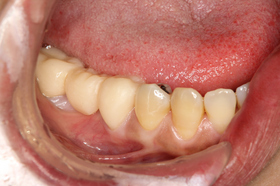

写真は、下顎奥歯のブリッジの支台歯(ブリッジの土台になっている歯)に虫歯ができてしまったため、ブリッジを除去し虫歯の治療を行った後に、新しいブリッジを作ることになった患者さんです。

支台歯周囲の歯肉が退縮し、歯根が露出しているのが認められます。

露出した歯根面は、知覚過敏もあり、虫歯やプラークコントロールのことも考慮して、クラウンで覆うことにしました。

写真は、ブリッジを除去し虫歯治療を行い、ブリッジの仮歯を装着した状態です。